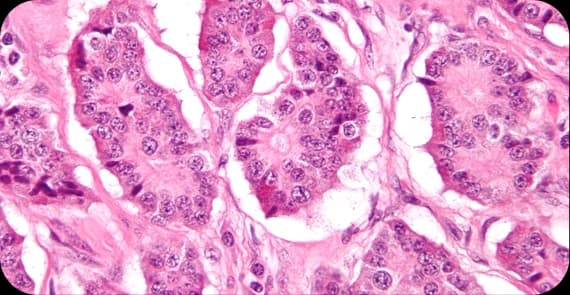

There are different types of prostate cancer depending on the cells from which the tumour arises.

The most common type, originating in the glandular cells of the prostate.